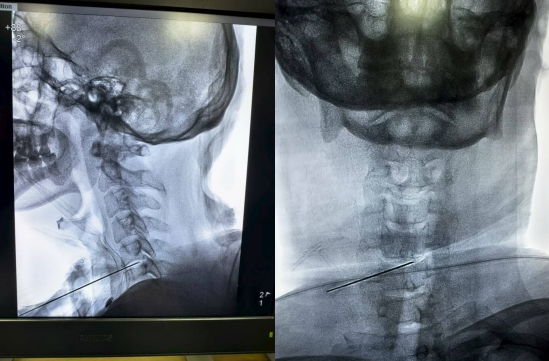

一台非同寻常的C型臂引导下的三叉神经半月节毁损术

早晨查完房匆忙赶到了疼痛门诊,这一天没什么特别的,依然是熙熙攘攘,社会服务科安排的志愿者依然是耐心的安抚着焦急的病人,一位满头白发的瘦弱老太太坐在门口的椅子上休息,头几乎埋在大腿中间,没有特别留意,一天漫长的门诊就要开始了,加油,奥特曼......门诊进行到了一半,护士张敏过来悄悄对我说:“门口一个老太太看起来疼的很厉害,让她先加个塞吧?”这在疼痛门诊是常见现象,志愿者给其他病人解释过后,帮助家属把病人...